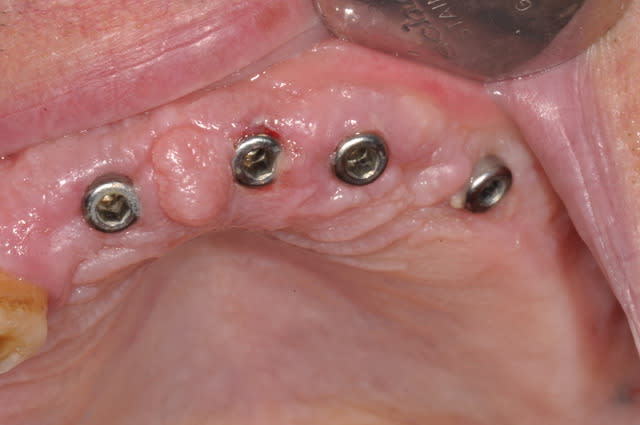

Je te mets la cicatrisation à 24h,çà me plait bien, ce sont des implants Léone

Essayer les implants champions me titille, si je peux les adapter à mes guides